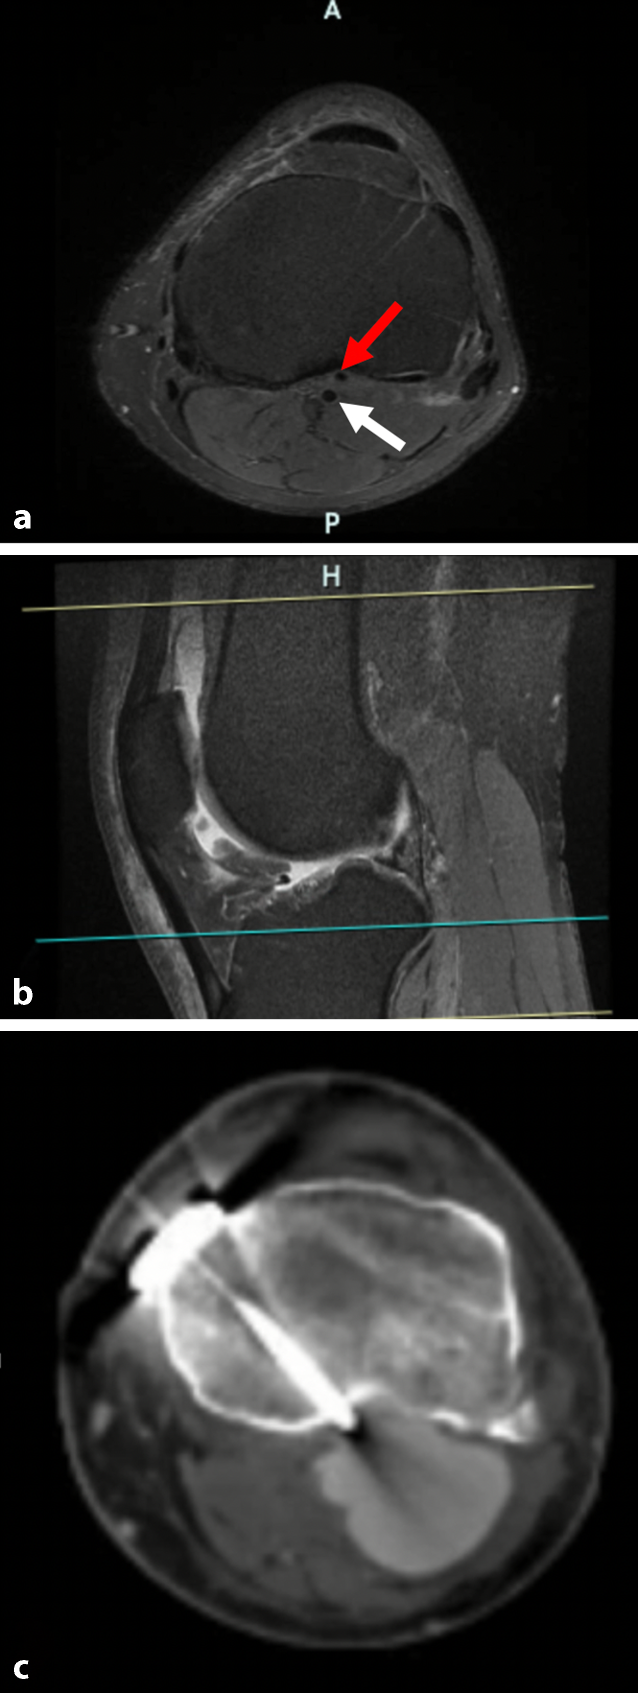

Da die Beschwerden nach der Revisionsoperation weiterhin bestanden, erfolgte eine internistische Konsiliaruntersuchung mit erneuter dopplersonografischer Untersuchung und dabei wurde ein V. a. Aneurysma der A. poplitea festgestellt. Der Patient wurde daraufhin direkt in eine Klinik für Gefäßchirurgie verlegt. Ein Pseudoaneurysma der linken A. poplitea von ca. 3,9 × 4,2 × 5,9 cm Größe wurde mittels Computertomografie-Angiografie (CTA) bestätigt (Abb. 5). Nach gesicherter Diagnose und bei drohendem Kompartmentsyndrom erfolgte die Aneurysmaausschaltung durch die Implantation eines Stentgrafts und die Anlage eines trunkalen A.-tibialis-anterior-Venenbypass (nach Überstentung des hohen Abgangs der A. tibialis anterior). Zudem wurden die Kompartmentspaltung sowie Vakuumtherapie (VAC-Therapie) am linken Unterschenkel durchgeführt. Im weiteren Verlauf erfolgte der Wundverschluss durch die Spalthauttransplantation. Der weitere postoperative Verlauf war komplikationslos.

Abb. 5

Präoperative MRT-Bildgebung (a, b) und postoperative CT-Bildgebung (c) des linken Kniegelenks. a Die axiale Schnittbildgebung zeigt den hoch aberranten Abgang der A. tibialis anterior (roter Pfeil) aus der A. poplitea (weißer Pfeil) ventral vom M. popliteus, das Gefäß befindet sich in unmittelbarer Nachbarschaft zum posterioren Cortex der proximalen Tibia, b die sagittale Schnittbildgebung zeigt die Höhe der axialen Schnittbildgebung (mit der blauen Linie) und die Lagebeziehung der hoch aberranten A. tibialis anterior zum posterioren Kortex der proximalen Tibia, c Pseudoaneurysma der linken A. poplitea nach medial öffnender tibialer Umstellungsosteotomie (HTO), das Aneurysma befindet sich im Verlauf der proximalen Schraube, ein Schraubenüberstand von ca. 3 mm wurde gemessen

Wenn man die präoperative MRT-Bildgebung in diesem Fallbeispiel genau analysiert, kann man den hoch aberranten Abgang der A. tibialis anterior aus der A. poplitea erkennen. Wenn man sich die postoperative CT-Untersuchung anschaut, sieht man, dass das Pseudoaneurysma sich im Verlauf der proximalen Schraube befindet (Abb. 5). Hier sieht man auch einen Schraubenüberstand von ca. 3 mm, obwohl eine monokortikale Lage der proximalen Schrauben intraoperativ angestrebt und die bikortikale Lage der Schraube weder in der intraoperativen Durchleuchtung noch in der postoperativen Röntgenkontrolle festgestellt wurde. Aus diesem Grund geht man CT-morphologisch davon aus, dass die Gefäßverletzung a. e. durch Bohren oder ggf. bei Messung der Schraubenlänge entstanden sein kann.